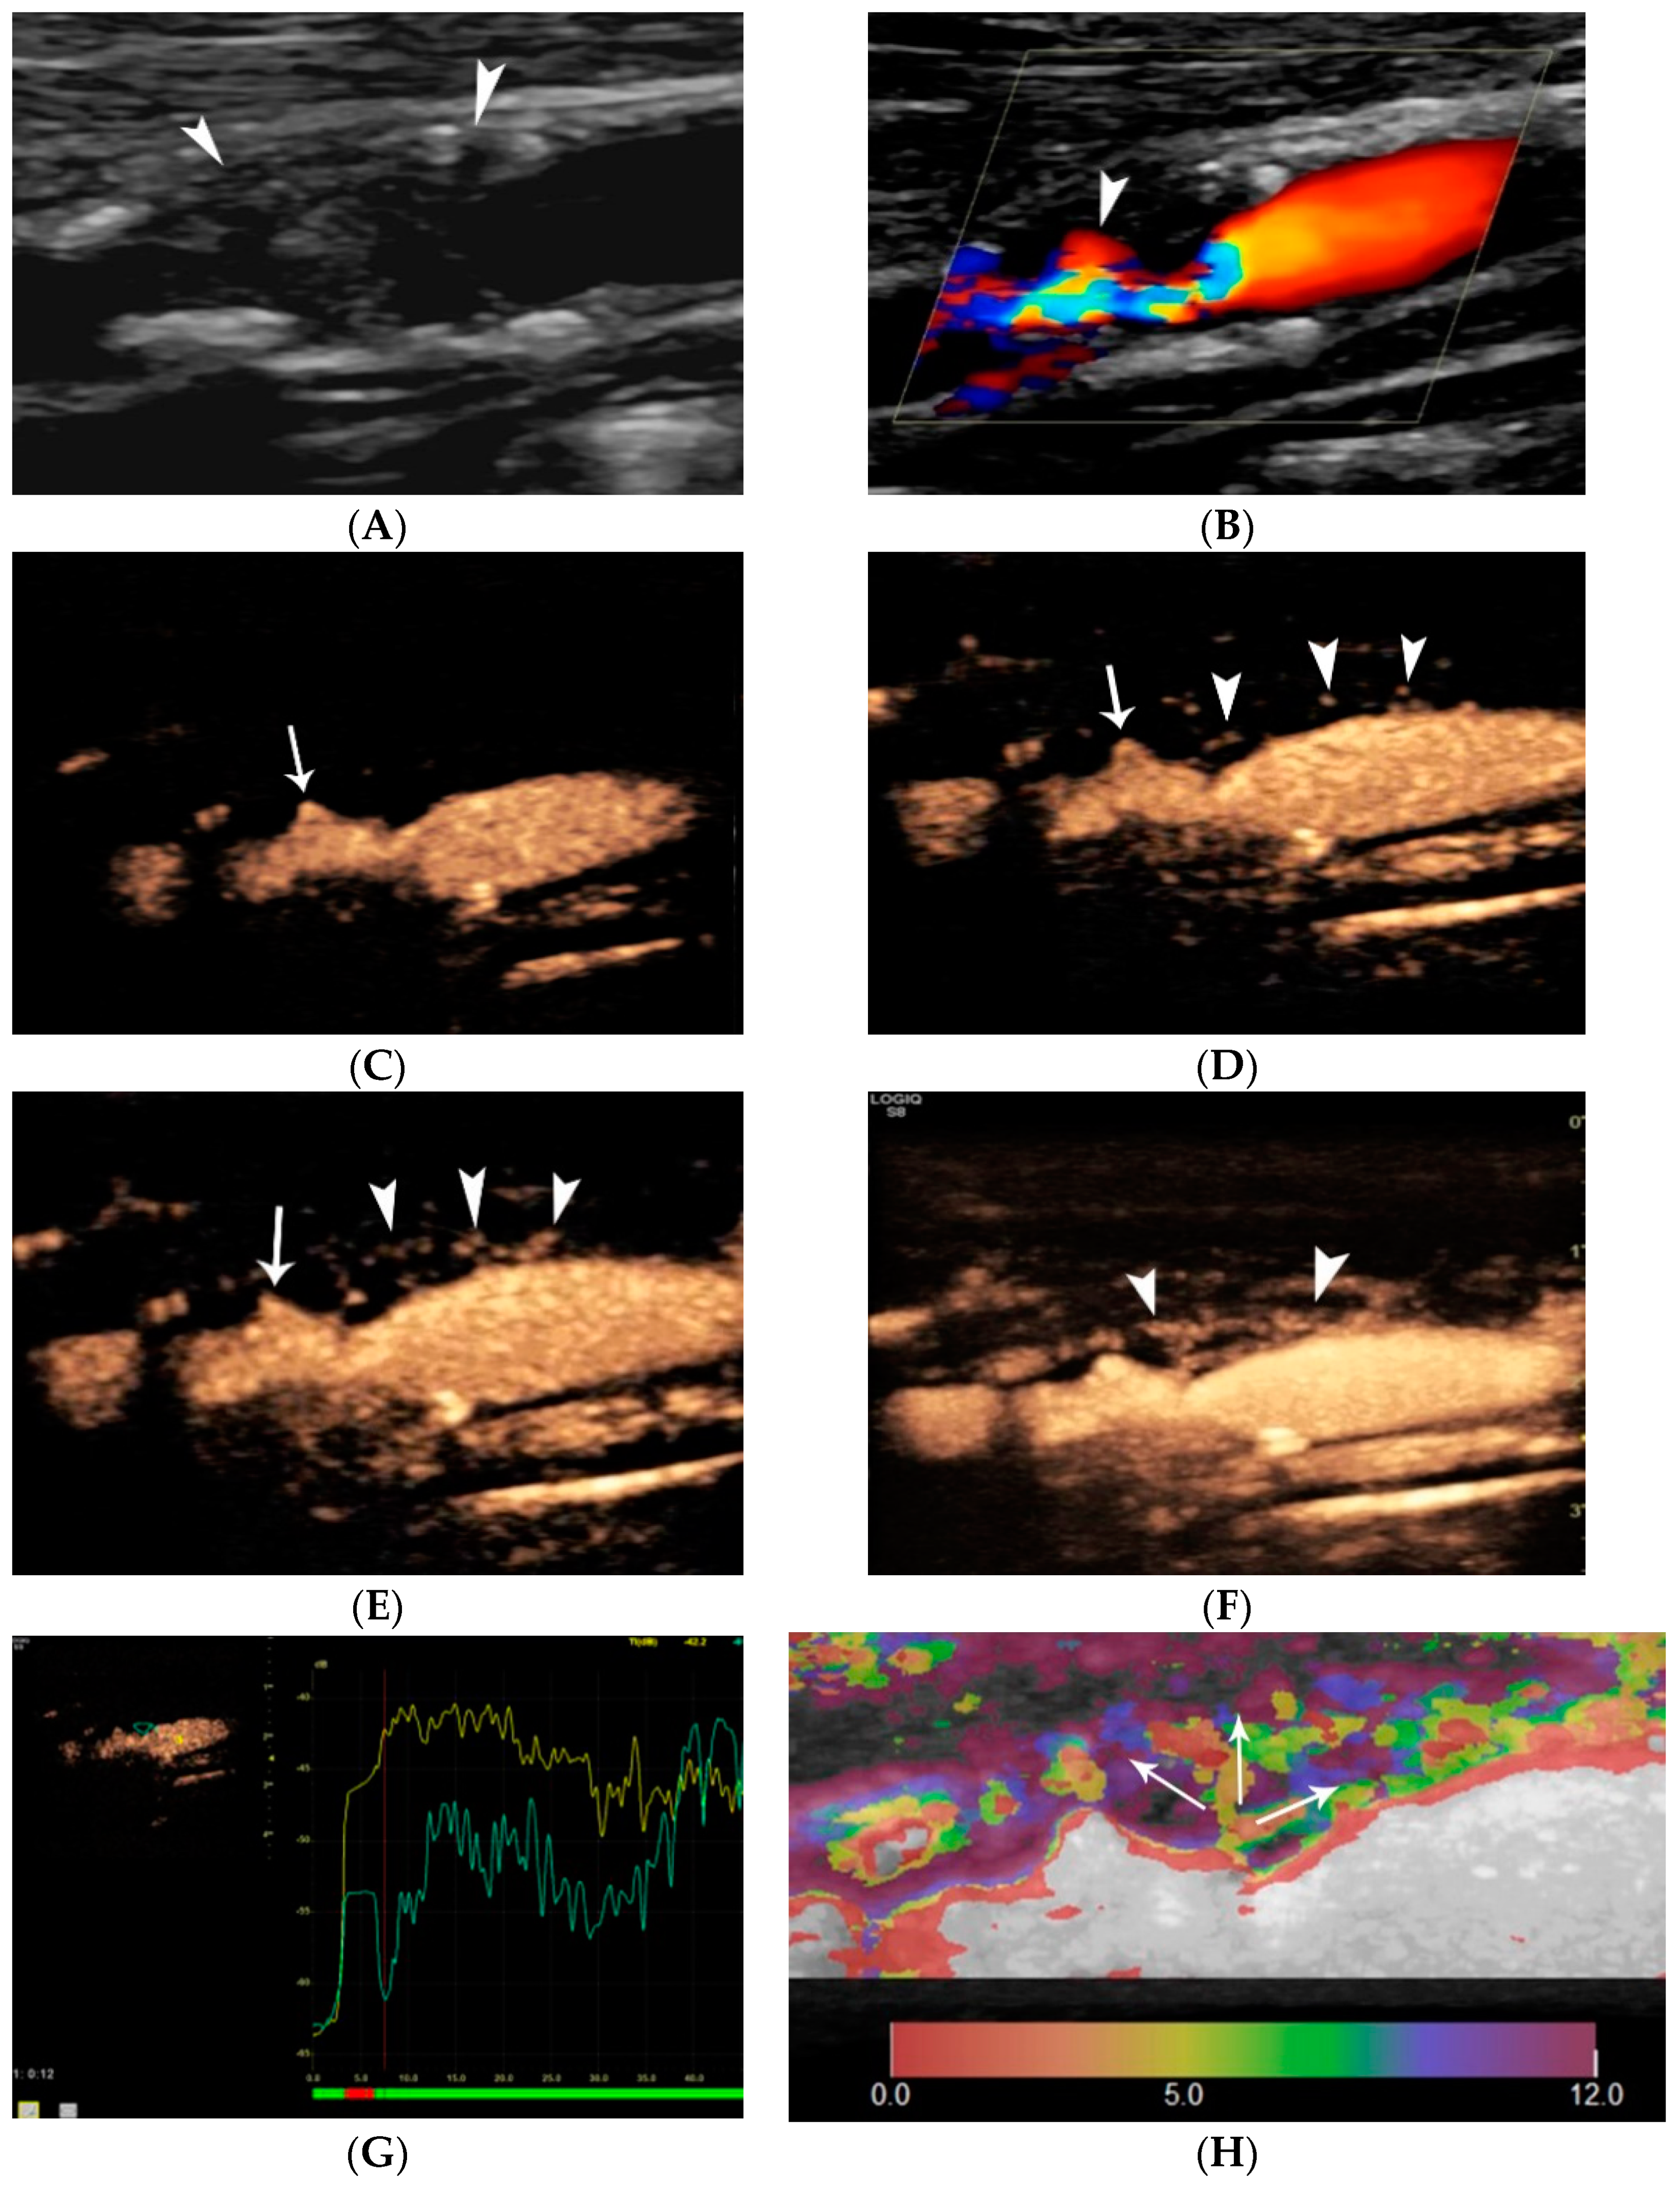

5. Elastography of Carotid Atherosclerotic Disease

4. Contrast-Enhanced Ultrasound (CEUS)